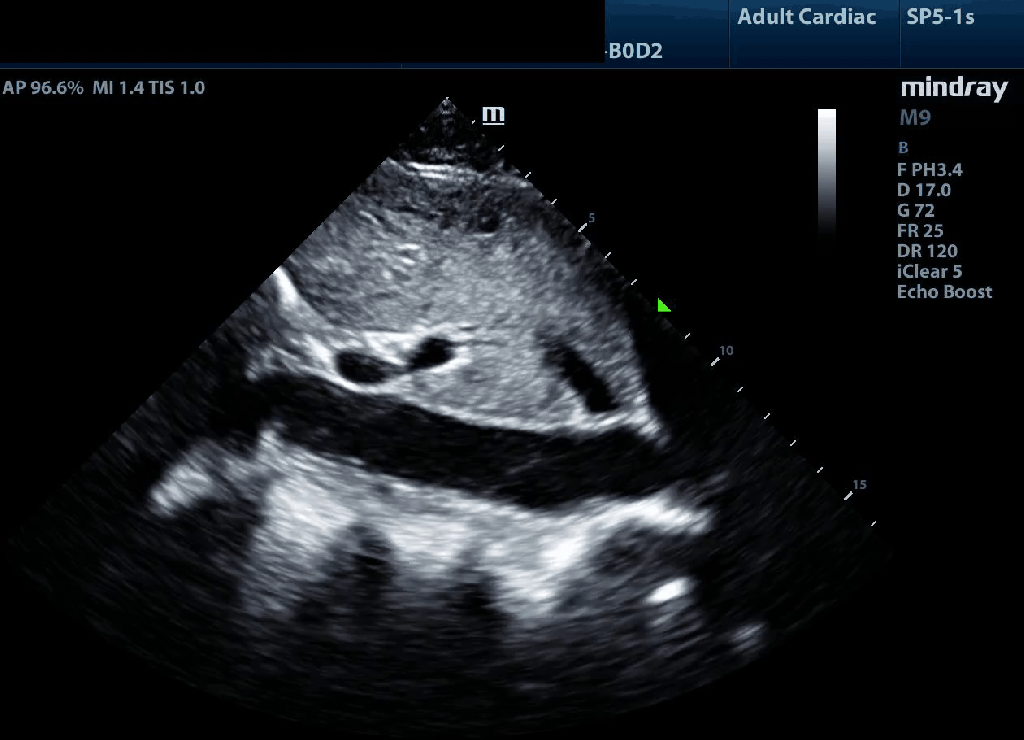

Parasternal Long Axis

Position patient in left lateral decubitus if possible. Typically acquired left parasternal border between the 2-4th interspace with probe marker in the 9-10 o’clock position. Left ventricle should be perpendicular to the transducer. The LV apex should not be visible. MV leaflet tips should be roughly at the center of the image. Ensure sufficient depth to capture the descending aorta. Gross LV function, RV/aortic root/LA dilation, valvular abnormalities, and pericardial effusion are assessable from this view.